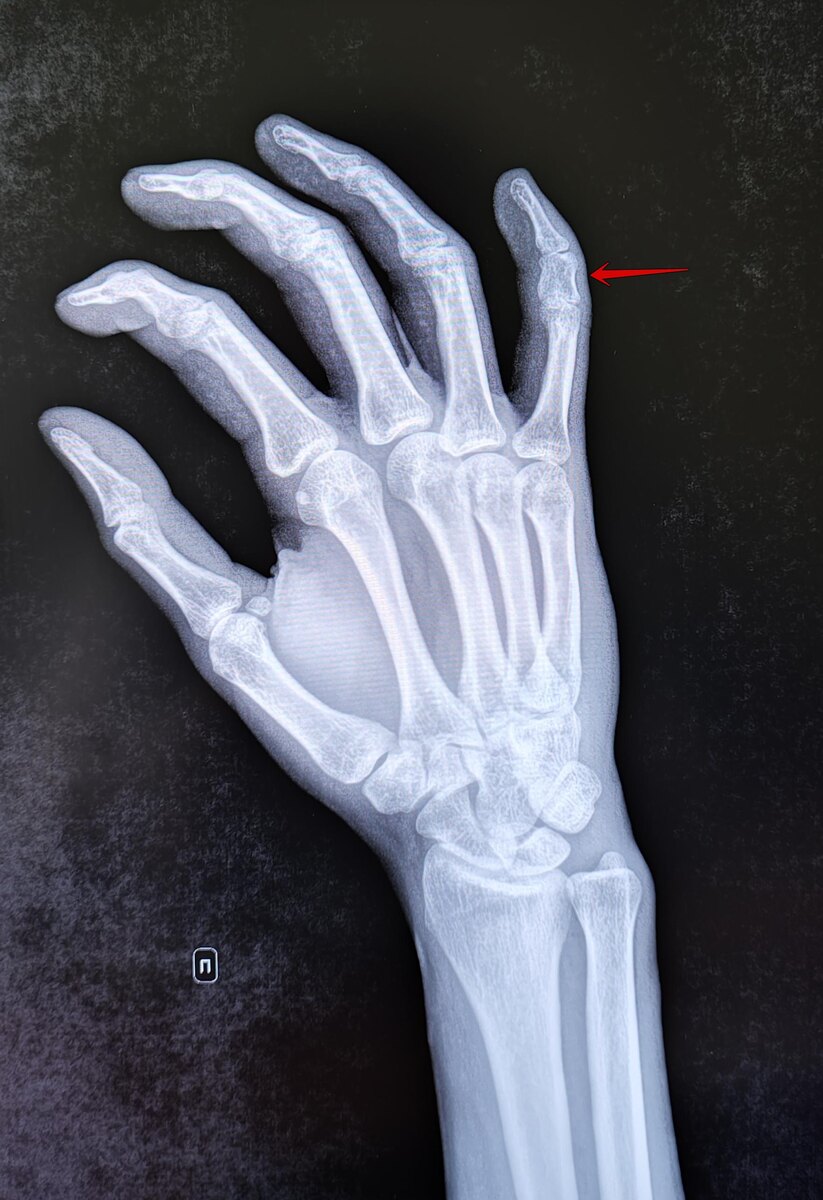

Это врождённая аномалия развития, характеризующаяся укорочением пальцев кистей и/или стоп из-за недоразвития или отсутствия фаланг. На Р-граммах правой кисти в 2х проекциях: травматических, деструктивных изменений не выявлено. Структура костной ткани не изменена. Средняя фаланга пятого пальца укорочена, утолщена. По остальным отделам кисти-без явной костной патологии. Заключение: Врожденная аномалия развития правой кисти- брахидактилия (брахифалангия) средней фаланги пятого пальца правой кисти. Категория годности с данным диагнозом по ст.67(Отсутствие, деформации, дефекты кисти и пальцев), г) при наличии объективных данных без нарушения функций-Б3(годен к в/сл с незначительными ограничениями). https://t.me/MME_SurgeryRadiolodgy https://vk.com/club223629464

Это врождённая аномалия развития, характеризующаяся укорочением пальцев кистей и/или стоп из-за недоразвития или отсутствия фаланг.

На Р-граммах правой кисти в 2х проекциях: травматических, деструктивных изменений не выявлено. Структура костной ткани не изменена. Средняя фаланга пятого пальца укорочена, утолщена. По остальным отделам кисти-без явной костной патологии.

Заключение: Врожденная аномалия развития правой кисти- брахидактилия (брахифалангия) средней фаланги пятого пальца правой кисти.

Категория годности с данным диагнозом по ст.67(Отсутствие, деформации, дефекты кисти и пальцев), г) при наличии объективных данных без нарушения функций-Б3(годен к в/сл с незначительными ограничениями).